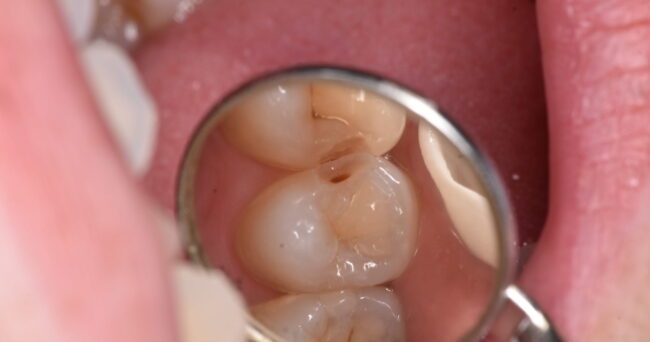

今回は歯と歯の間の虫歯です。むしろ、今回「も」ですね(´・_・`)

解説を入れずに写真を並べてみようと思います。それでは、下の写真をご覧ください。

おそらく、3つ目の写真で虫歯を取り終わったと思う方が多いのではないでしょうか?正確には4つ目が取り終わりです。

3つ目よりも4つ目の方が歯が白いのがわかるでしょうか?実際には4つ目の方が削っているので、深いわけです。深い、ということは写真を撮る時に暗くなりやすいはずです。それにも関わらず、4枚目の方が明るい=3枚目の汚染されている範囲が広い、ということです。

今回もX戦ではそれほどはっきり映っていませんでした。ちなみに↑のような事態はよくあります。

X線は確定診断として、よく使われますが、X線だけであるなしの判定は危険である、と言えます。レントゲン撮影をして、映ってないから虫歯がない、と言われたとしても、実は間に広がる虫歯がある、ということをご理解ください。

ちなみに、レントゲン撮影でわからない場合の最終判定は目視、つまり「目で見て確認」になります。こればかりは、どの歯医者がしっかり診れるか、という判断は難しいです。